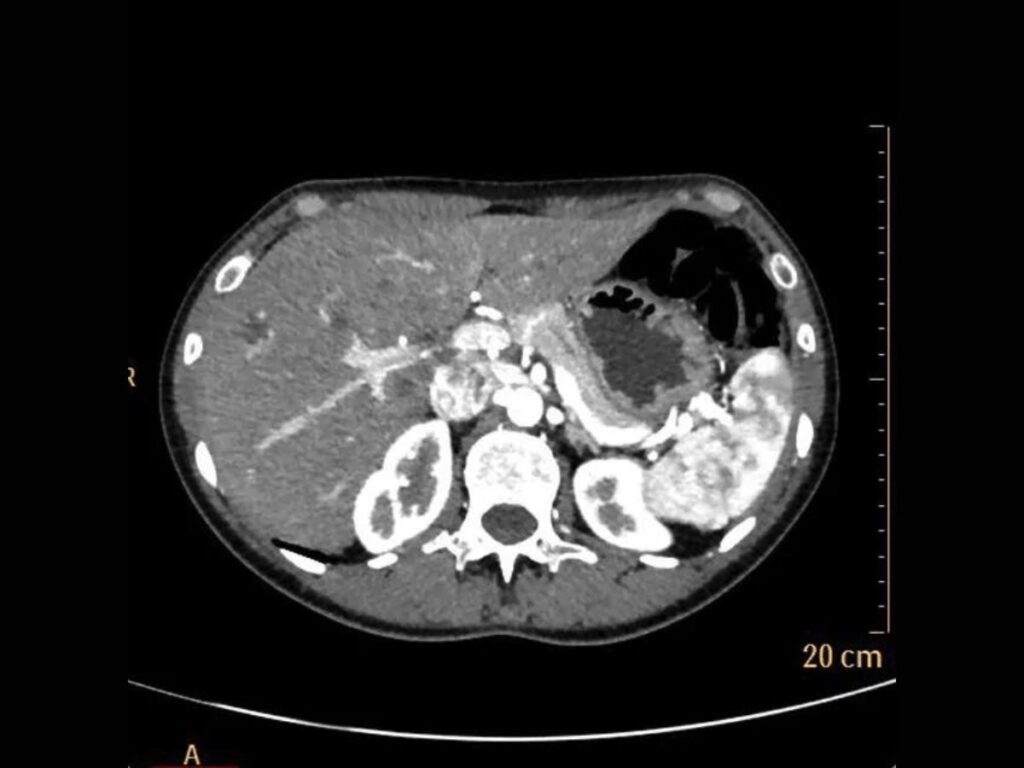

L’osservatore che accede a questo disco si trova davanti a un’estensione algoritmica, dove la biografia clinica del soggetto è scomposta in una serie di sezioni assiali, coronali e sagittali: una stratificazione ipertestuale che permette di navigare all’interno della carne. Si vede qualcosa che rivela la vulnerabilità e la complessità della nostra struttura biologica, trasformando l’intimità organica in un riflesso esterno, condivisibile e consultabile. La grana di queste immagini è la traccia concreta di un’interazione tra la téchne e il vivente, dove il contrasto tra i bianchi e i neri definisce i confini di un’identità che non risiede più soltanto nella psiche, ma nella capacità della macchina di rendere navigabile l’invisibile.

MZ: Nella tua pratica quotidiana, sezioni il corpo umano attraverso la risonanza magnetica per scopi diagnostici. In quale momento la “fetta” anatomica smette di essere un dato clinico per trasformarsi, ai tuoi occhi, in un reperto che può essere riletto secondo connotazioni concettuali o estetiche?

DS: Esiste un’estetica delle immagini per il medico? Sì. Si tratta tuttavia di un’estetica “morale”, vale a dire intimamente connessa allo scopo dell’immagine, la rappresentazione di quella parte di corpo umano che mi accingo a valutare. Ancora direi che nel caso della risonanza magnetica (ma vale per qualsiasi metodica di diagnostica per immagini), ci si confronta con un’immagine attesa, quella data dalla memoria di tutte le immagini “normali”, cioè sane, accumulate nella mente con l’esperienza. Il “sano” è una perfezione attesa, tuttavia non geometrica, non ideale, fondata piuttosto sulla memoria delle immagini corrispondenti ad una “perfezione biologica”. Esiste comunque uno stupore per la qualità delle immagini, legato al dettaglio anatomico (“sembra una sezione anatomica” è una delle frasi più ricorrenti) o alla maggior evidenza delle anomalie (frutto di una maggior risoluzione di contrasto).